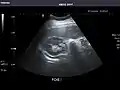

Left kidney

Kidneys: Right and left kidneys measure 11.5 cm and 12 cm in length respectively. No hydronephrosis. Small left lower pole kidney cyst.